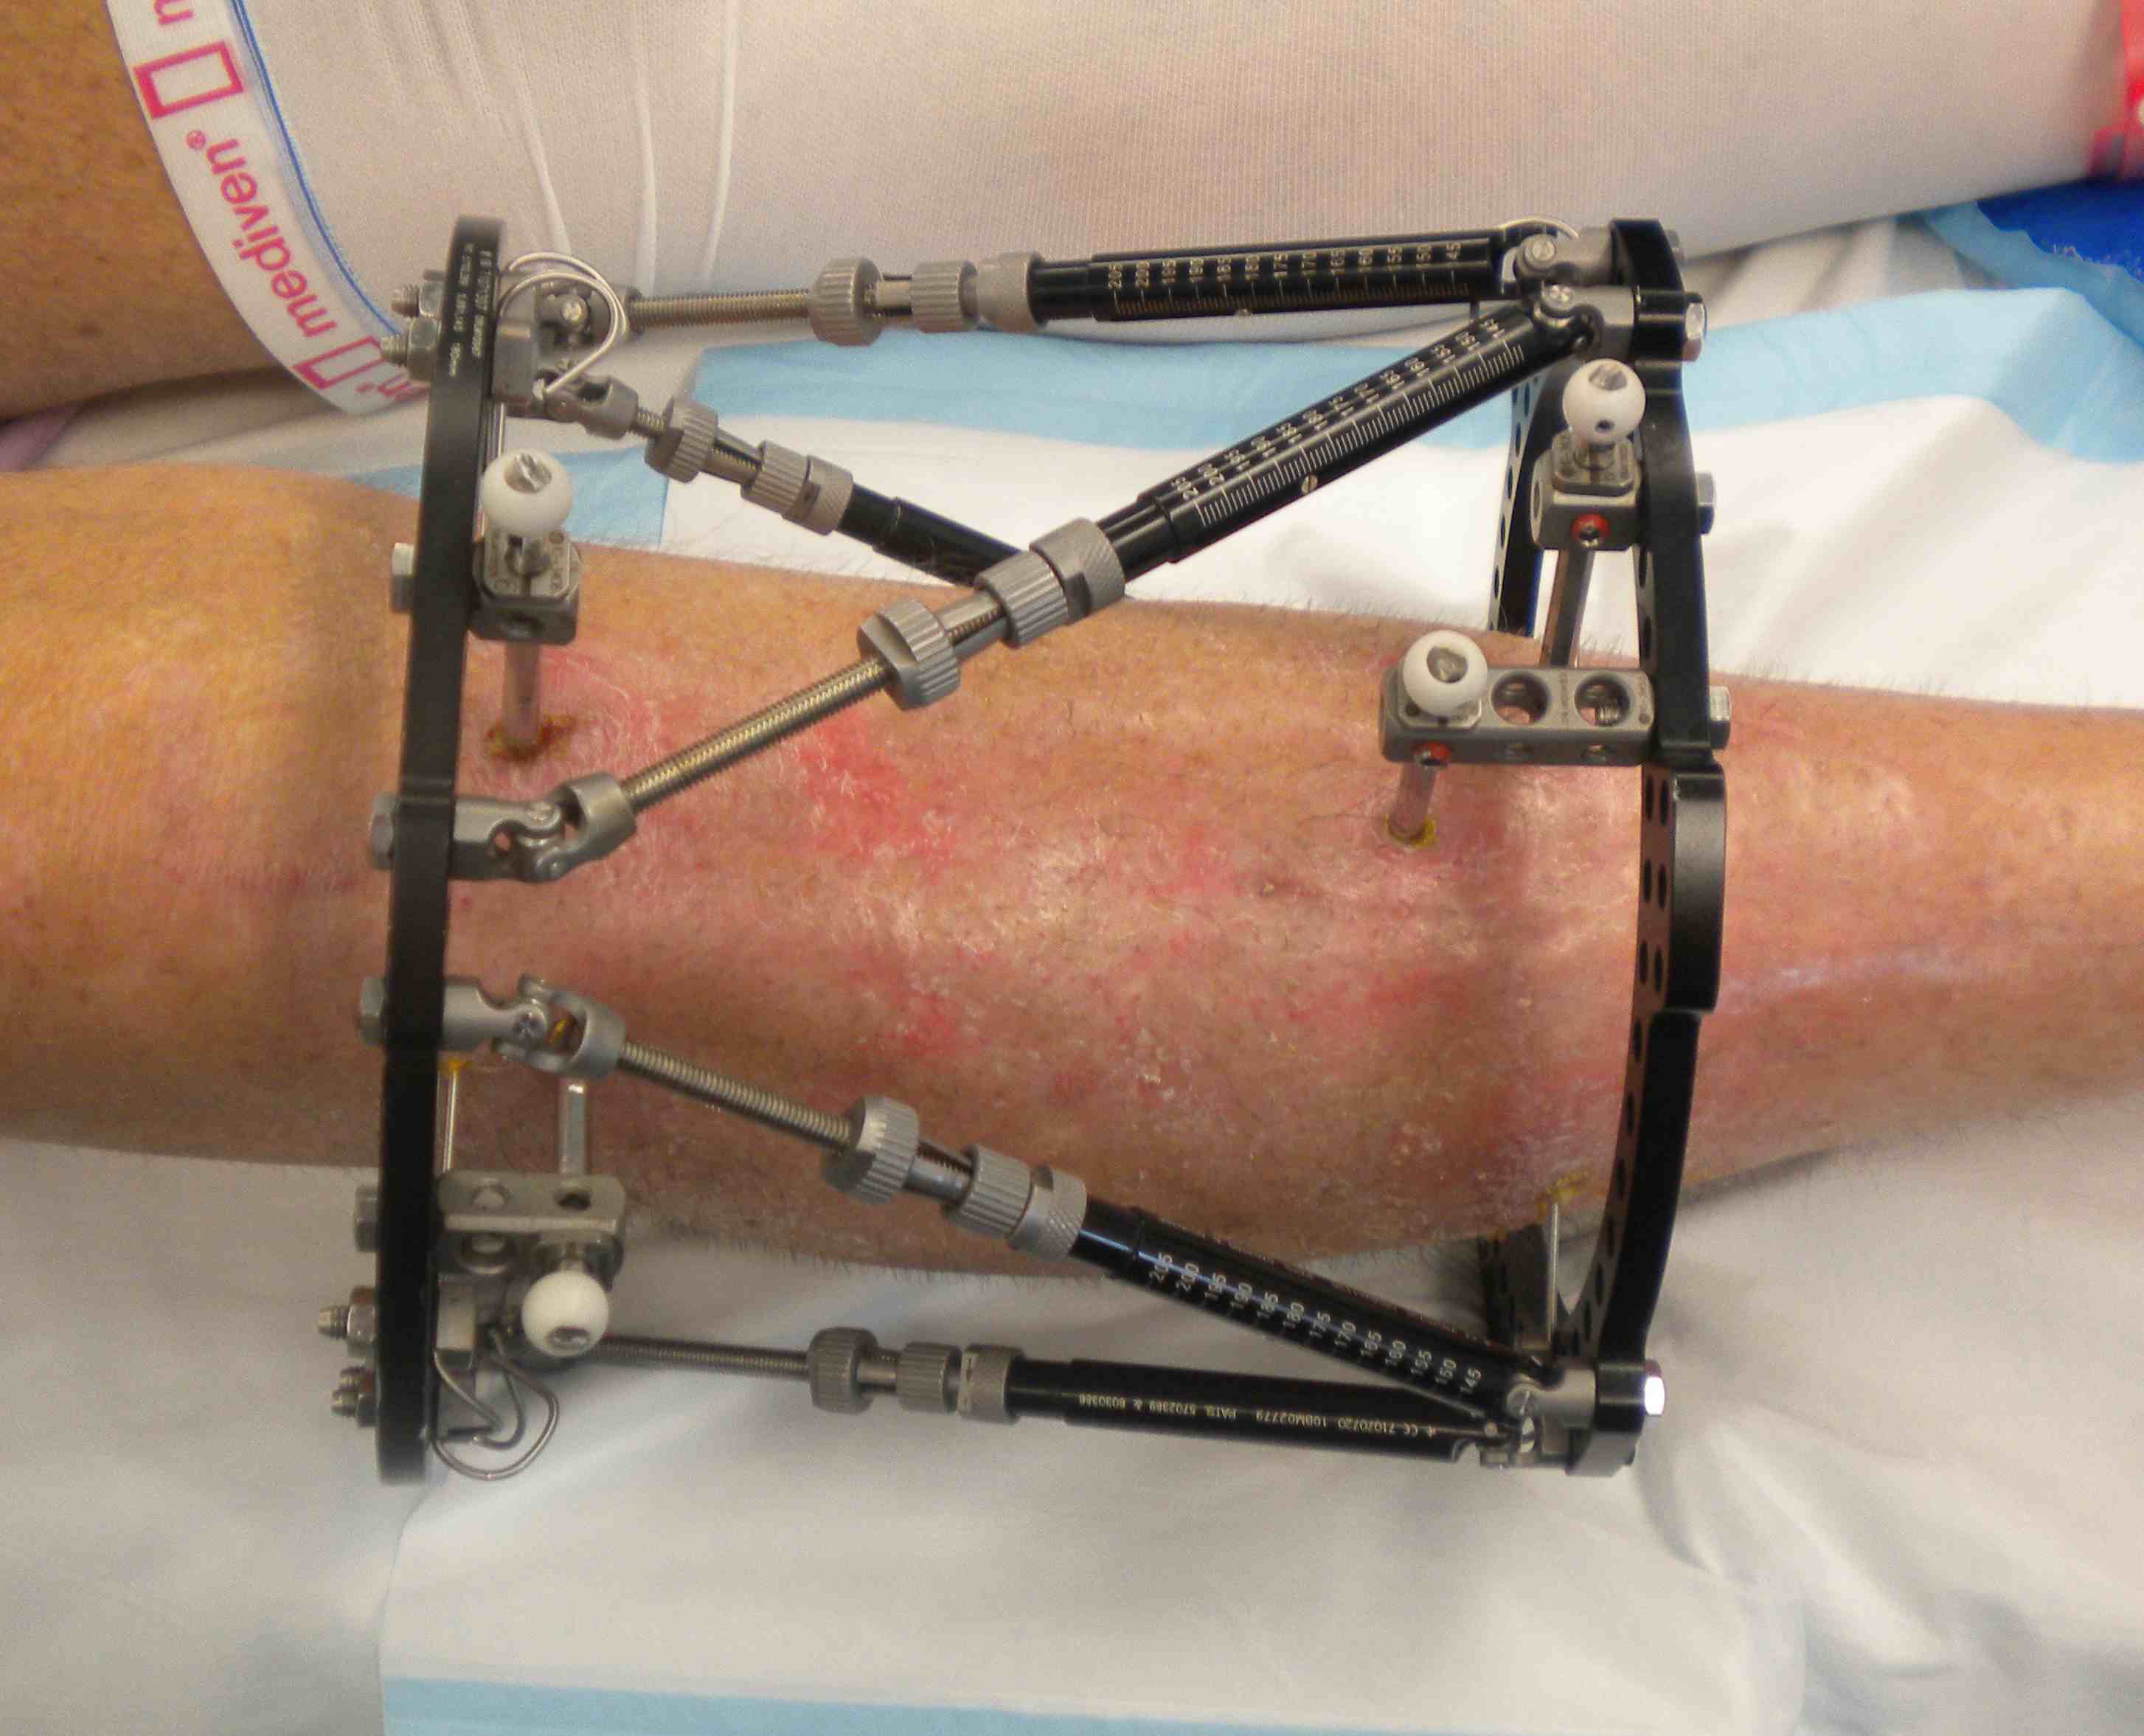

Deformity correction

Poor soft tissues

- prohibit ORIF

Non union

Infected non uniion

Malunion / deformity

Bone loss / bone transport / LLD